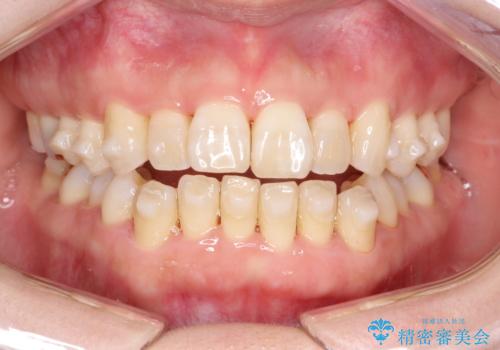

- 上下の前歯の開き(開咬)と上下前歯にガタつき(叢生)が見られます。

マウスピース矯正ではメカニクス的に開咬へのアプローチが容易です。

インビザラインの特色を生かした歯牙移動計画を作成し、非抜歯にて治療を行いました。